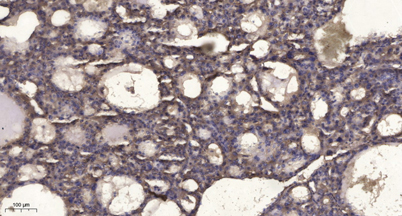

IHC

IHC-p 1:50-300